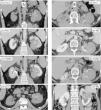

Se presenta como un tumor periférico circunscrito (pequeño y homogéneamente sólido o mayor quístico-hemorrágico) o como una lesión infiltrante e invasora de venas, con peor pronóstico.

Por su baja densidad vascular, el realce es menor que en otras neoplasias renales, lo que facilita su caracterización. En tomografía computarizada puede no realzar de manera concluyente, y entonces es indistinguible de un quiste hiperatenuante. La ecografía con contraste y la resonancia magnética son más sensibles para detectar vascularización. Son además característicos un patrón vascular específico, hipointensidad en T2, restricción de la difusión del agua y aumento de señal en fase opuesta.

It presents as a circumscribed peripheral tumor (small and homogeneously solid or larger and cystic/hemorrhagic) or as an infiltrating lesion that invades the veins, which has a worse prognosis.

Due to their low vascular density, papillary renal cell carcinomas enhance less than other renal tumors, and this facilitates their characterization. On computed tomography, they might not enhance conclusively, and in these cases they are impossible to distinguish from hyperattenuating cysts. Contrast-enhanced ultrasonography and magnetic resonance imaging are more sensitive for detecting vascularization. Other characteristics include a specific vascular pattern, hypointensity on T2-weighted images, restricted water diffusion, and increased signal intensity in opposed phase images.